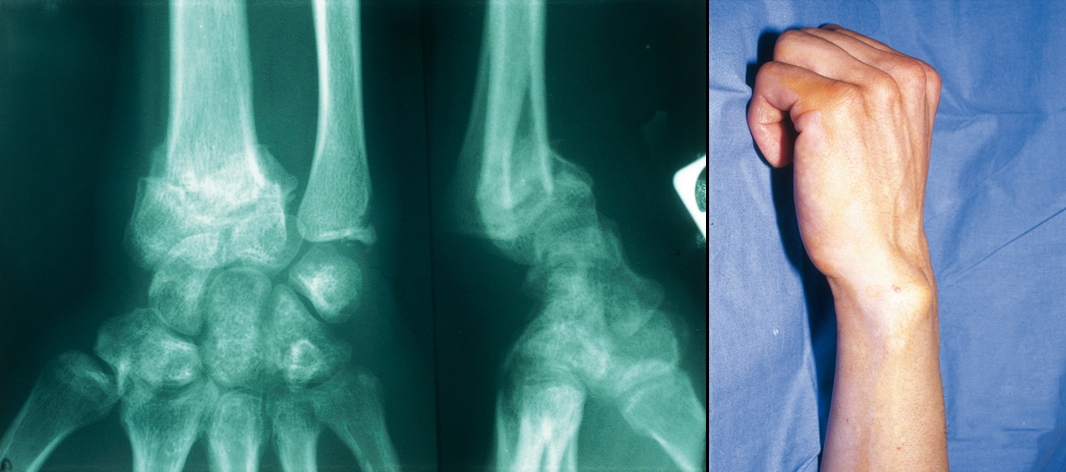

Cal vicieux de face et de profil. Noter l’angulation et le raccourcissement majeurs du radius. Les consolidations en position vicieuse de l’extrémité inférieure du radius [cals vicieux articulaires et (ou) extra-articulaires] ont des conséquences fonctionnelles parfois très invalidantes sur les mouvements du poignet, mais très souvent aussi sur la pronosupination des 2 os de l’avant-bras.